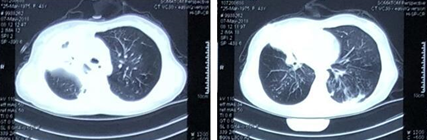

• 复查胸部CT示右肺上叶多发空洞,右肺中叶实变影,左肺下叶背段少许支气管扩张合并感染(图2)

图片

图2  患者胸部CT